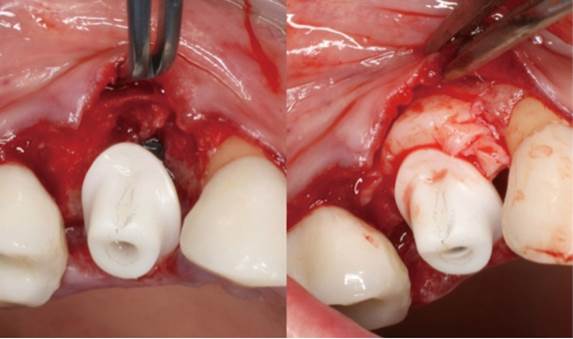

Clinical case: Extraction, immediate implant placement, & provisionalization

- Courtesy of Dr. Iulian Filipov, Romania -

AnyRidge, R2GATE, guided surgery, immediate placement, immediate provisionalization, initial stability, Dr. Iulian Filipov, #25, maxillary posterior, immediate loading, Mega ISQ

Products:

AnyRidge implant system, R2GATE, MEGA ISQ, Digital prosthesis